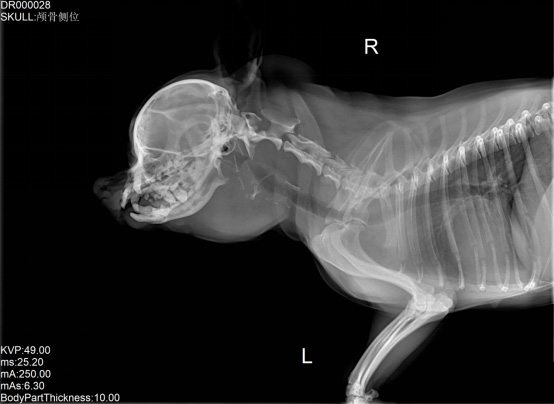

寵物DR是專業(yè)用于寵物X光拍攝的數(shù)字化X射線檢查,輔助寵物醫(yī)生進(jìn)行及時(shí)精確的診療。寵物DR主要包括五大主要部件,數(shù)字X光探測(cè)器,高壓發(fā)生器,球管,機(jī)架,寵物專用的DR工作站軟件。寵物DR由于采用數(shù)字技術(shù),自動(dòng)成像處理,模擬X線圖像向數(shù)字化X線圖像的轉(zhuǎn)變。寵物DR與傳統(tǒng)模擬X光機(jī)相比有什么優(yōu)勢(shì)呢?采集時(shí)間10毫秒以下,成像時(shí)間僅為3秒,較高的空間分辨力和低噪聲率,提高了病灶的檢出率,避免漏診誤診等問題。減少X線對(duì)人體照射的不良影響寵物DR照片是您最佳的選擇。提高寵物醫(yī)生工作效率,總而言之,選擇寵物DR是寵物醫(yī)院的最佳選擇。寵物醫(yī)學(xué)影像學(xué)實(shí)現(xiàn)全數(shù)字化和無膠片化升級(jí)發(fā)展提高技術(shù)水平。